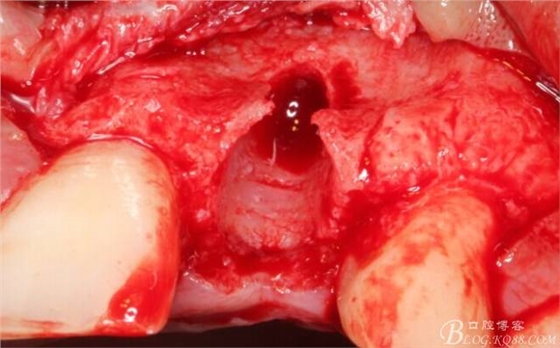

再次翻瓣。

先行粘骨膜減張,取自體血液。

根方用取骨鉆取自體骨。

旋入一長(zhǎng)兩短3顆鈦釘。

將自體骨與BIO-OOS骨粉混合植到術(shù)區(qū),蓋生物膜。